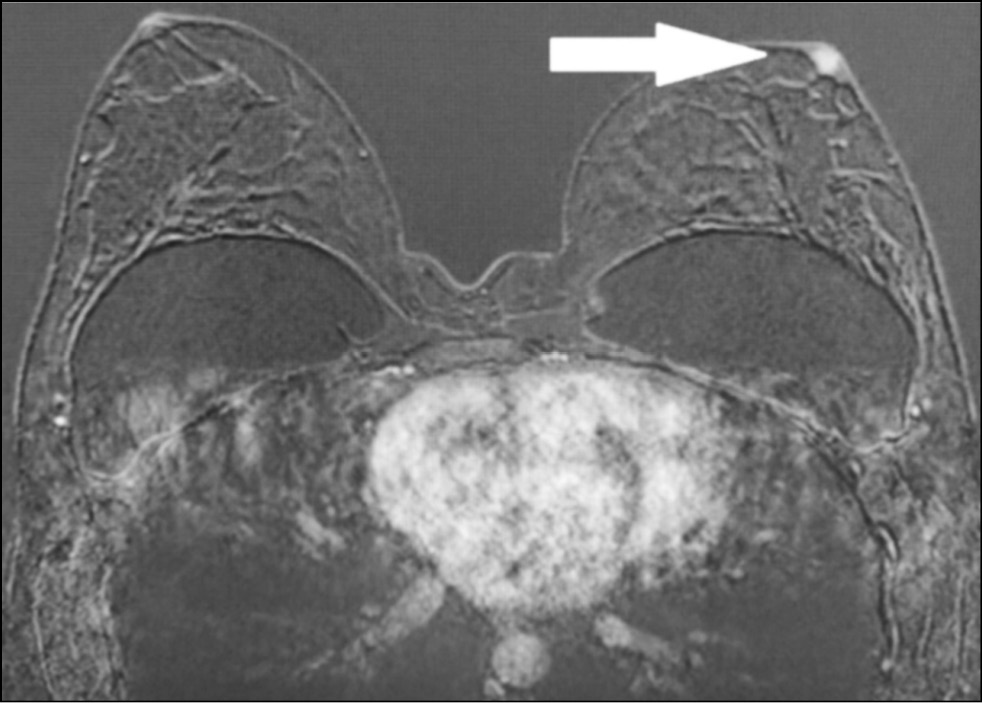

A 59-year-old patient complained of erosive changes in the nipple (Fig. 1). Physical examination revealed erythema, erosion, and nipple retraction. Doppler ultrasonography with color flow mapping revealed increased blood flow in the nipple projection (Fig. 2). Mammography findings were normal. To assess the extent of disease spread, breast MRI with contrast enhancement was performed. The early postcontrast series (Fig. 3) and maximum intensity projection (MIP) images (Fig. 4) showed a segmental contrast retroareolar area from the nipple level to posterior breast sections. Ultrasound-guided core biopsy followed by immunohistochemical analysis revealed Paget’s disease of the nipple with high-grade intraductal carcinoma in situ. Receptors for estrogen (G3 ER) and progesterone (PR) were negative. Oncogenic protein Ki-67 was 45%.

Figure 3. Magnetic resonance imaging of Paget’s disease (early enhancement phase): the retroareolar area of segmental enhancement from the nipple level to the posterior breast (arrow).

In a 43-year-old patient who had no complaints, the breast was examined by MRI to assess the integrity of implants. The asymmetric enhancement of the left nipple was accidentally found (Figs. 9 and 10). Three-year dynamic observation did not reveal any unfavorable changes.

Figure 9. Magnetic resonance imaging (early postcontrast series): asymmetric contrast accumulation in the left nipple; normal finding (arrow).